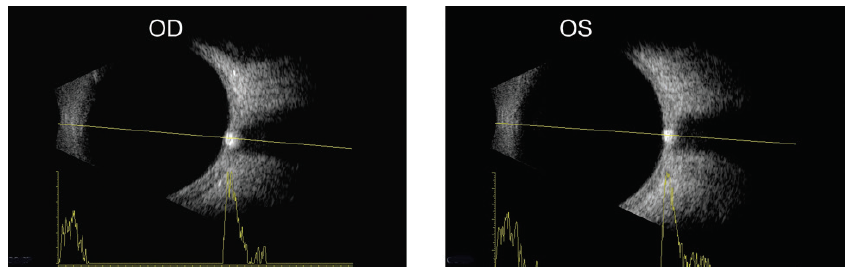

Due to the evolving course of papilledema, the Frisén scale was developed to describe papilledema in clinically meaningful stages.13 B-scan ultrasonography can assist in diagnosis of IIH by measuring the diameter of the optic nerve sheath.16 The diameters in primary gaze and in 30° eccentric gaze are compared, and a 20% reduction in diameter in eccentric gaze (30° test) bilaterally is considered a positive test result, indicating increased subarachnoid fluid surrounding the optic nerve (Figure 1). Additionally, B-scan ultrasonography can aid in differentiating pseudopapilledema from papilledema by identifying optic disc drusen (Figure 2).17